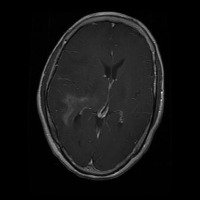

This project has created a labeled MRI brain tumor dataset for the detection of three tumor types: pituitary, meningioma, and glioma. The dataset contains 2443 total images, which have been split into training, validation, and test sets. The training set has 1695 images, the validation set has 502 images, and the test set has 246 images.

- Image types: MRI scans

- Pituitary tumor

- Meningioma tumor

- Glioma tumor

- No Tumor

- The images have been labeled by medical experts using a standardized labeling protocol.

- The labels include the type of tumor and the location of the tumor.